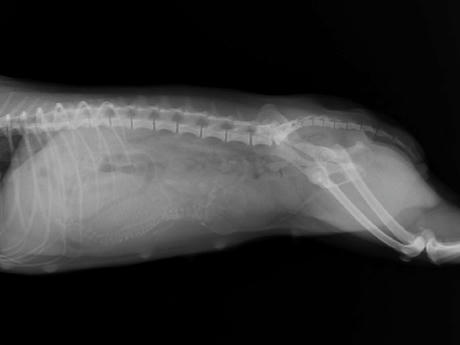

急にお腹が大きくなって、ぐるぐる鳴るようになったので、獣医さんにいってきました。

レントゲンを撮ってもらったら、良く育ってる大きくて元気な子が1わんでした。

エヴァは骨盤の産道が広いのでギリギリ自然分娩できるかも知れないけど

帝王切開になる可能性は低くないと言われてしまいました・・ ^^;)/

予定日は来週の月曜日から木曜日あたりなんだそうです。